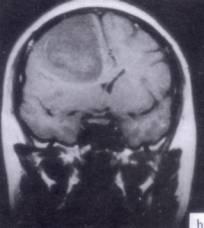

病历摘要:??患者男性,52岁。头痛伴呕吐2月,呕吐呈喷射性。既往身体健康。体检:神清,表情淡漠,反应迟钝,双眼底视神经乳头明显水肿,左鼻唇沟稍浅,左腹壁...

问题 病历摘要:??患者男性,52岁。头痛伴呕吐2月,呕吐呈喷射性。既往身体健康。体检:神清,表情淡漠,反应迟钝,双眼底视神经乳头明显水肿,左鼻唇沟稍浅,左腹壁反射减弱,左上下肢肌力4级,左Babinski征(-)。 下列关于脑叶切除术范围的叙述哪些是正确的?